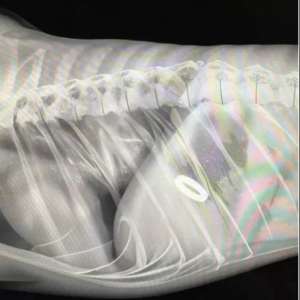

14 февраля в Челябинске парень купил кольцо для предложения, но его планы сорвал… пёс Беляш, проглотивший украшение. 🐾💍

Не теряя присутствия духа, молодой человек уговорил ветеринара написать в справке «рекомендацию» ответить согласием. 😄❤